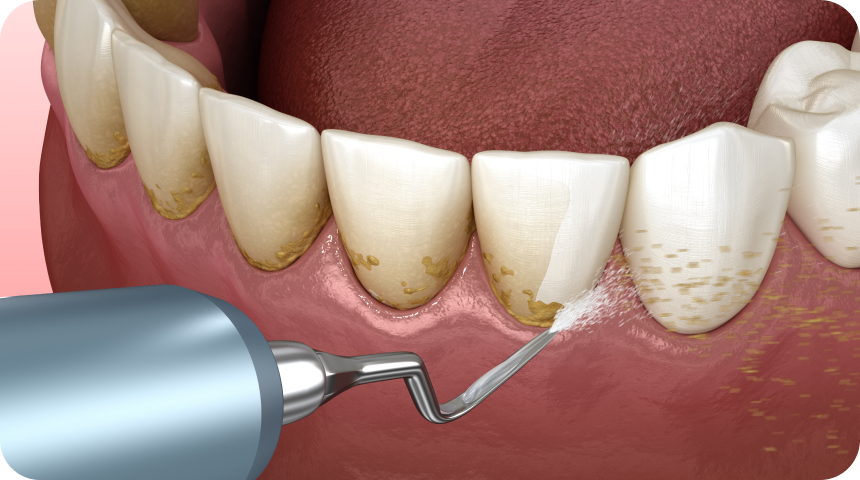

Le détartrage est un nettoyage dentaire qui permet d’enlever le tartre pour éviter la gingivite ou encore la parodontite.

Grâce au détartrage dentaire et au polissage, le dentiste peut retirer tout le tartre fixé à vos dents pour prévenir les maladies parodontales ou gingivales.

Avant de réaliser un détartrage dentaire, le dentiste vérifie les antécédents médicaux du patient. Une fois que le diagnostic est terminé, il réalise un détartrage qui peut être soit un nettoyage profond des dents, soit un nettoyage de calcul dentaire à ultrasons, soit un détartrage supra gingival. Le détartrage permet de retrouver des dents et des gencives saines.